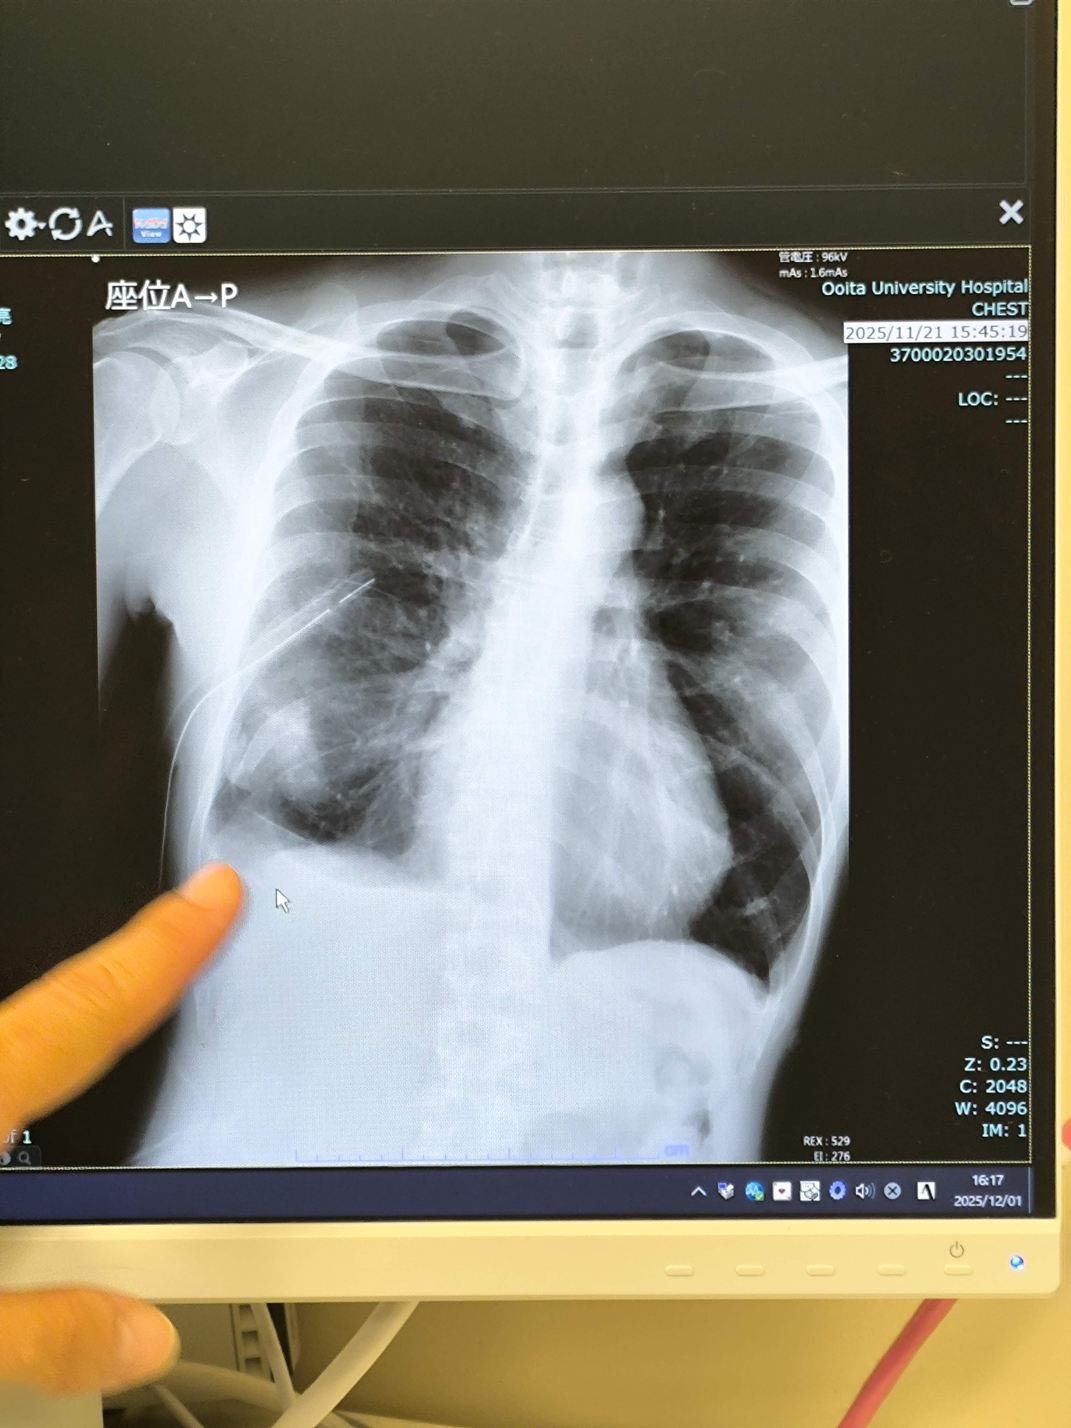

体内に管が入っているのがお分かり頂けるでしょうか。

これがドレインというものです。

肺周辺の空気、体液を排出するための管で、私の右肺には、直径2cmほど、長さ16cmのチューブが11月13日から26日まで、13日間、突き刺さっていたのです。